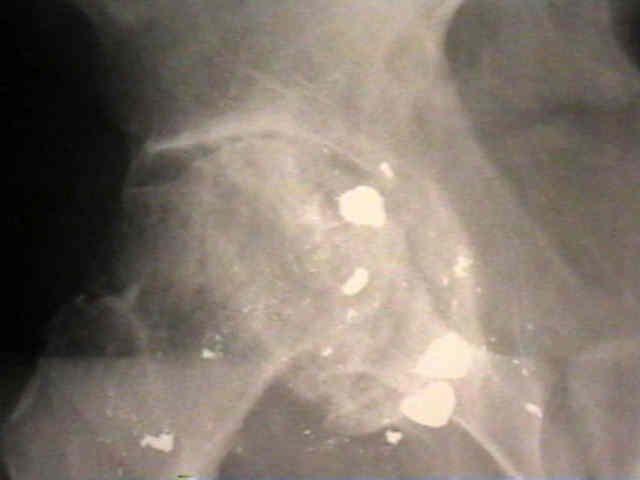

Case Example

- 35-year-old male w/ near anklyosed hip following a GSW to the hip;

- preoperative films appeared to indicate that little or no medialization was necessary;

- postoperative films, however, indicate that the cup was lateralized (hence, reaming was inadequate);

- in retrospect, the radiographs which are rotated externally (like an iliac oblique) tend to falsely minimize the necessary amount of medialization where as X-rays which are rotated internally (like an obturator oblique), tend to over-estimate the necessary amount of medialization